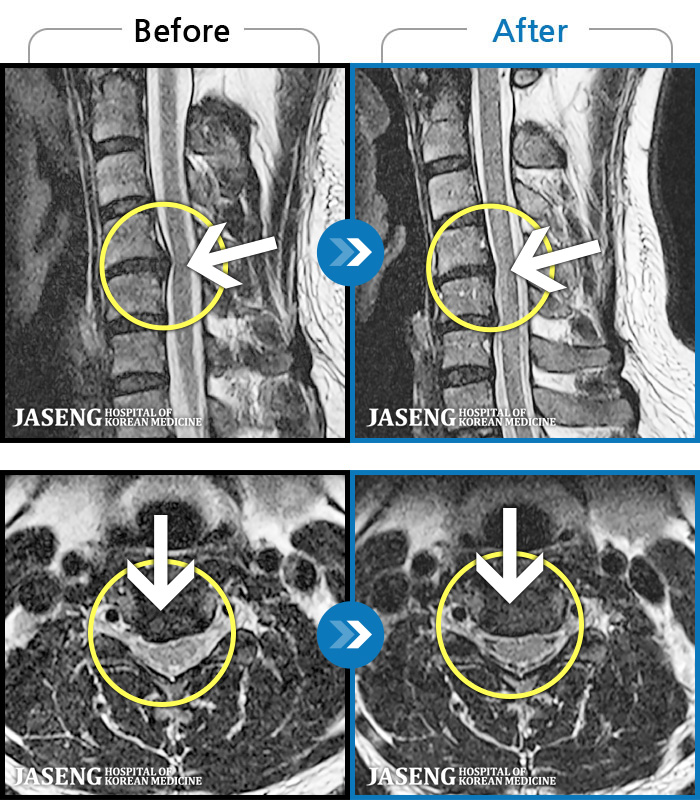

1,228건의 MRI 전후 사진으로 터진 디스크 흡수 사례를 확인하세요.

하지 저림과 통증이 개선되어서 일상생활이 너무 즐겁습니다. |

| 병의원명해운대 | 질환명허리디스크 | 담당의김상돈 원장 | 날짜2025.02.05 | 조회수23,808 |

[해운대] 23.09.18~25.01.27

※ 환자분에게 사전 동의를 받아 동일 조건에서 촬영되었으며, 개인에 따라 치료 후 부작용이 발생할 수도 있으니 사전에 의료진과 상담 후 치료를 진행하시기 바랍니다.